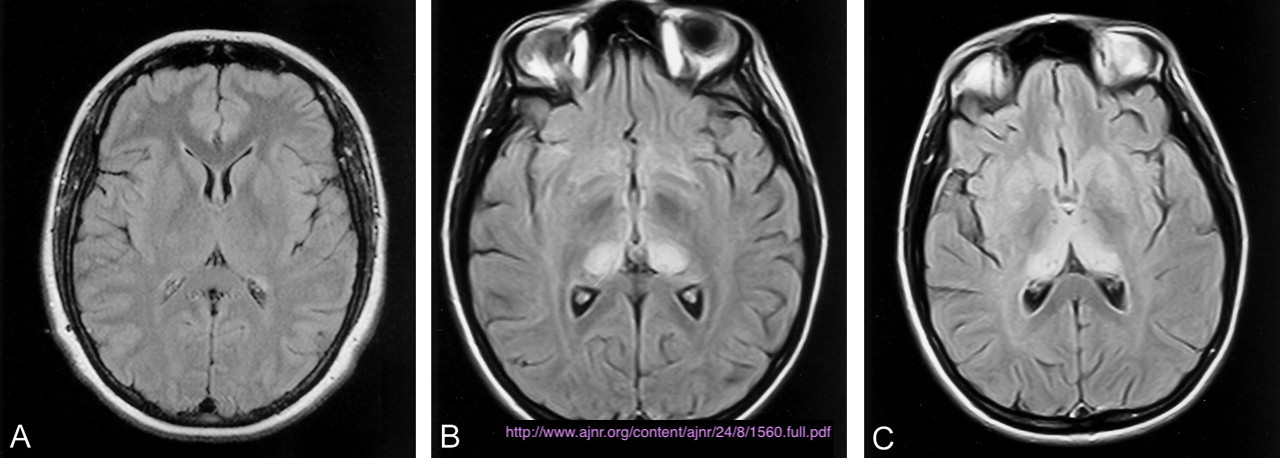

Cerebral fat embolism

Note the multiple sites of oedema and haemorrhage, involving the brain stem and corpus callosum as well as subcortical white matter and left cerebral peduncle. High FLAIR signal is also seen in the dorsal midbrain. EVD insitu.

Case Discussion

Diffuse axonal injury can be subtle on CT but have devastating consequences for the patient. This is a case of grade III injury (involvement of brainstem) and carries a poor prognosis.

Diffuse axonal injury (DAI), also known as traumatic axonal injury (TAI), is a severe form of traumatic brain injury due to shearing forces. It is a potentially difficult diagnosis to make on imaging alone, especially on CT as the finding can be subtle, however, it has the potential to result in severe neurological impairment.

The diagnosis is best made on MRI where it is characterised by several small regions of susceptibility artifact at the grey-white matter junction, in the corpus callosum, and in more severe cases in the brainstem, surrounded by FLAIR hyperintensity.

Diffuse axonal injury is characterised by multiple focal lesions with a characteristic distribution: typically located at the grey-white matter junction, in the corpus callosum and in more severe cases in the brainstem (see: grading of diffuse axonal injury).

MRI

MRI is the modality of choice for assessing suspected diffuse axonal injury even in patients with entirely normal CT of the brain 5,6. MRI, especially SWI or GRE sequences, exquisitely sensitive to paramagnetic blood products may demonstrate small regions of susceptibility artefact at the grey-white matter junction, in the corpus callosum or the brain stem. Some lesions may be entirely non-haemorrhagic (even using high field strength SWI sequences). These will, however, be visible as regions of high FLAIR signal.